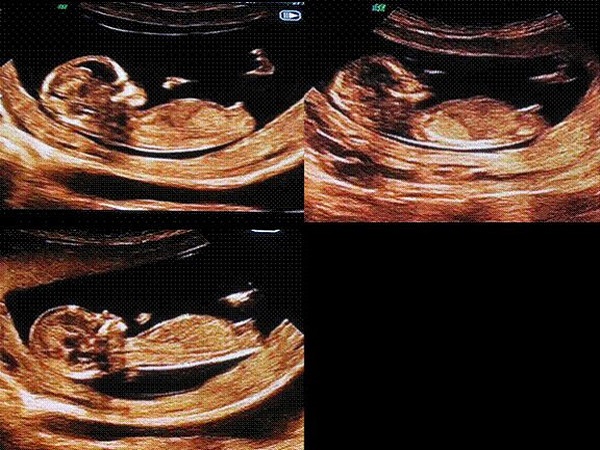

2、看胎儿的尾部

男孩:彩超图上如果胎儿的尾部翘的比较高,和背部形成了超过45度的夹角,那么怀的多半就是男宝宝;

B超图中尾部平平的就是生女孩

女孩:如果胎儿的尾部是平平的,和背部处于平行的状态的话,那么就说明孕妈妈怀的是个漂亮的女孩子。